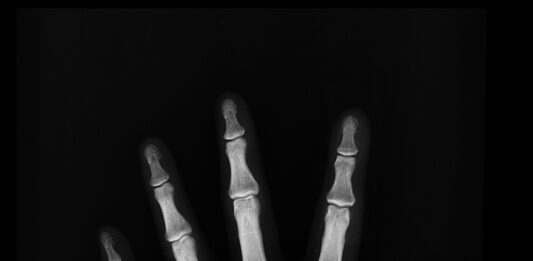

Lidé často nevědí, že jim řídnou kosti. Zlomeniny kvůli osteoporóze vážně ohrožují život

Zachytit v ordinacích praktických lékařů pacienty s rizikem řídnutí kostí dřív, než mají první zlomeniny – to je cíl Populačního programu časného záchytu osteoporózy, který v Česku odstartoval loni v dubnu. Doposud se ho zúčastnily tisíce pacientů. Ordinací, kde mohou lidé podstoupit specializované vyšetření kostí, navíc stále přibývá.